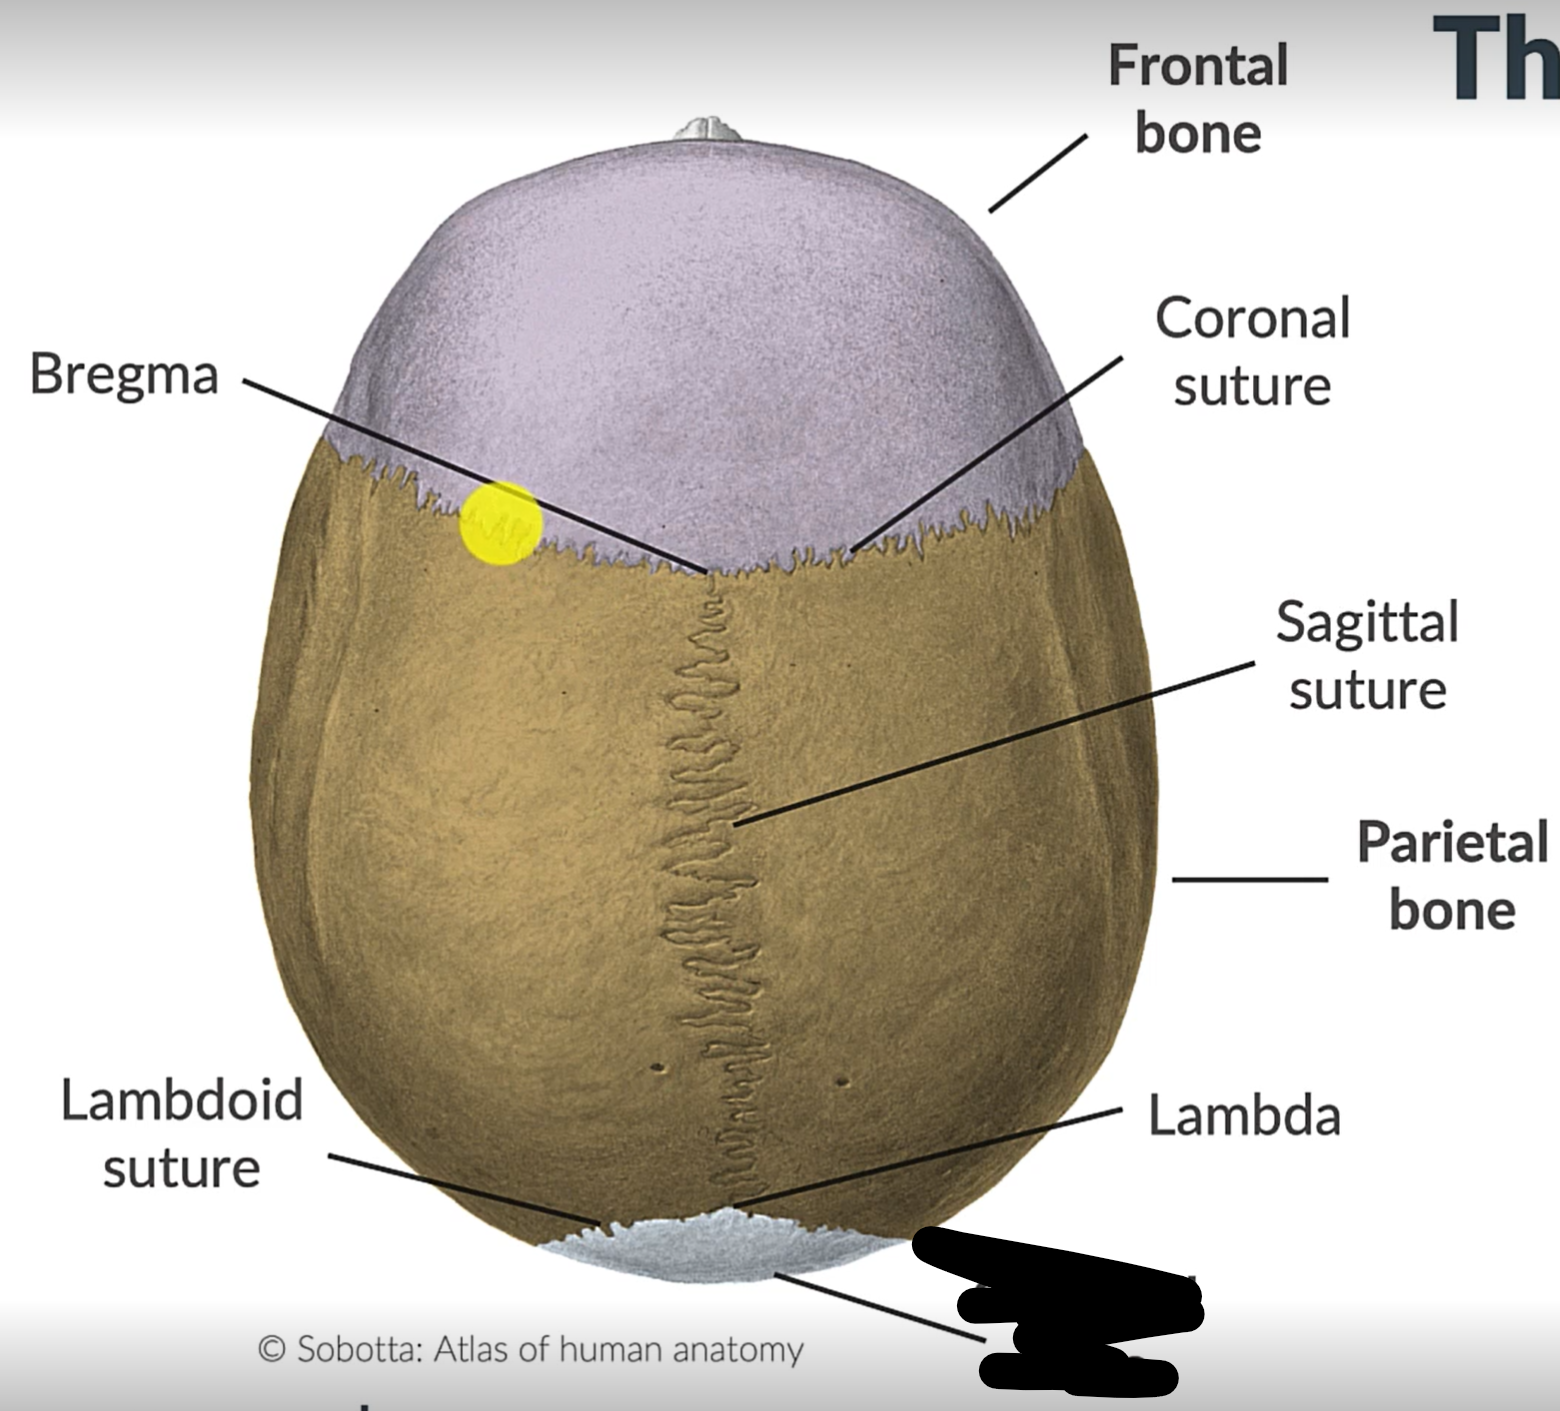

What are the 4 cranial sutures and what do they separate?

Lambdoid - separates occipital from parietal and temporal

Sagittal - extends between parietal bones

Coronal - divides frontal and parietal bones

Squamous - either side of cranium, separates temporal and parietal bones

Sagittal suture

Parietal bone

Lambdoid suture

Occipital bone

What is the point where the frontal and parietal bones meet?

Bregma

Lambda